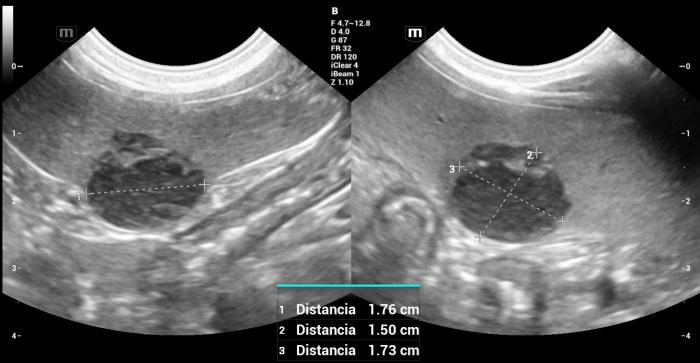

Hallazgos ultrasonográficos (modo B y doppler color): en el cuerpo esplénico, región perihiliar, se identificó un nódulo hipoecoico, bien delimitado, de contornos lisos, con dimensiones de 1.76 × 1.73 × 1.5 cm. La lesión deformaba la superficie visceral del bazo, sin evidenciar compromiso capsular (Figura6).

El Doppler color mostró vascularización positiva, principalmente periférica, sin patrones aberrantes evidentes (Figura7).

Hallazgos ultrasonográficos (modo B y doppler color): en la cola del bazo, se identificó un nódulo esférico, bien delimitado, de 2.12 × 2.09 cm, con ecogenicidad mixta: un centro predominantemente hipoecoico con pequeñas estructuras puntiformes hiperecoicas periféricas sugerentes de focos de mineralización o densificación tisular (Figura24).

La lesión deformaba la morfología de la cola esplénica y mostraba señal Doppler color positiva, principalmente periférica (Figura25).